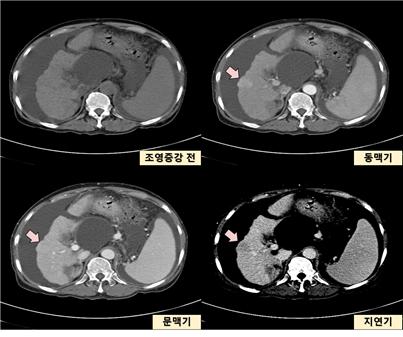

간은 인체에서 가장 큰 장기 중 하나로, 여러 가지 중요한 기능을 수행합니다. 간 질환은 매우 일반적인 문제로, 신속하고 정확한 진단이 필요합니다. 복부 CT를 통해 간의 경화, 종양, 지방간 등 다양한 문제를 확인할 수 있습니다. 특히 간암의 경우, CT 촬영은 초기 단계에서 종양의 크기와 위치를 평가하는 데 중요한 역할을 합니다. CT 이미지는 간 내 혈관과 주변 조직의 상태를 상세히 보여주기 때문에, 간암이 다른 장기로 전이되었는지 파악하는 데도 유용합니다.

간암: 조기 진단의 중요성

간암은 조기 증상이 거의 없기 때문에 진단이 늦어지는 경우가 많습니다. 그러나 복부 CT를 통해 초기 증상을 발견할 수 있다면, 치료 옵션이 훨씬 다양해집니다. 간암의 원인으로는 간염 바이러스 감염, 알코올 남용, 비만 등이 있으며, 이들 요인을 관리함으로써 예방할 수 있습니다. CT 촬영을 통해 조기에 간암을 발견하면, 간 절제술이나 간 이식과 같은 치료를 통해 생존율을 높일 수 있습니다.